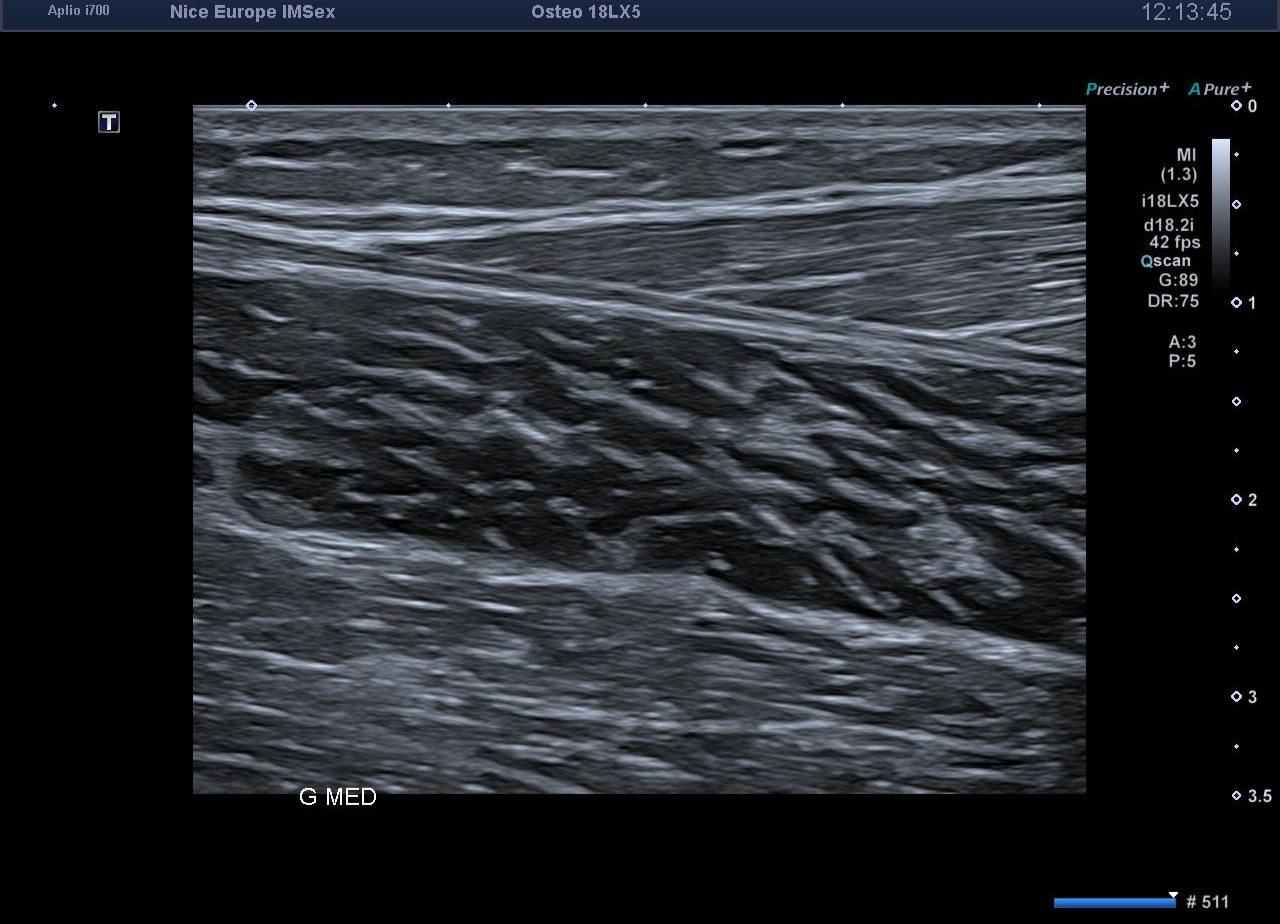

L’exploration statique haute résolution de la cheville et du mollet s'avère strictement normale. Les tendons calcanéens (d'Achille) présentent une écho-structure fibrillaire parfaitement conservée, sans épaississement focal, ni hyperhémie au Doppler énergie. L'exploration de la loge postérieure montre des ventres musculaires gastrocnémiens et soléaires volumineux mais d'échostructure normale, tout comme les jonctions myo-aponévrotiques. L'artère poplitée est perméable au repos, avec un flux Doppler triphasique physiologique.

À ce stade, l'examen clinique, obligatoirement réalisé de manière concomitante à l'exploration échographique, prend tout son sens. La palpation minutieuse des loges musculaires et la parfaite intégrité des tendons obligent l'opérateur à s'écarter de la prescription initiale pour rechercher une étiologie vasculaire à cette symptomatologie d'effort.

Devant ce morphotype athlétique et la négativité de l'examen statique, un test de provocation par échographie dynamique est entrepris pour rechercher un syndrome de l'artère poplitée piégée (ou piège poplité). Lors d’une manœuvre de flexion plantaire contrariée (mise en tension soutenue des muscles de la loge postérieure contre résistance), on objective en temps réel :